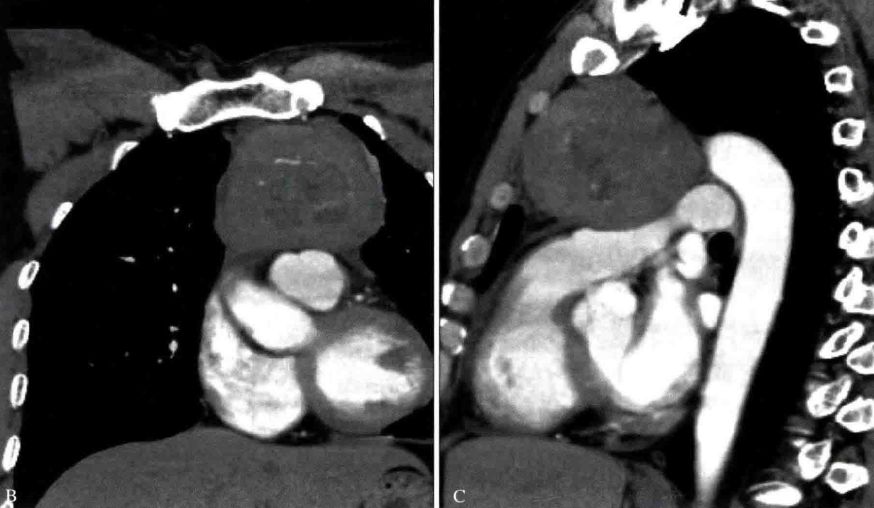

右上纵隔神经鞘瘤CT图像

a. 胸部正位片示右上纵隔脊柱旁圆形软组织密度影。b. CT平扫示右侧后上纵隔脊柱旁圆形软组织密度肿块影,密度均匀,边缘光整。c. CT增强示病灶轻度强化,密度均匀。d. CT增强矢状位重组图示肿块位于后上纵隔,与脊椎关系密切。

右中纵隔神经鞘瘤CT图像

MRI冠状位T1WI图像示胸椎右旁椭圆形病灶,病灶内部呈混杂信号,边缘呈高信号。